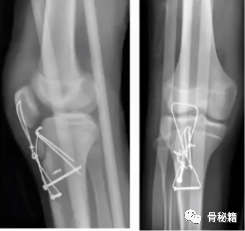

7、胫骨结节骨折

8、高段位假体周围骨折,如何捆钢板?

以下是几种不同的缠绕钢板的方法